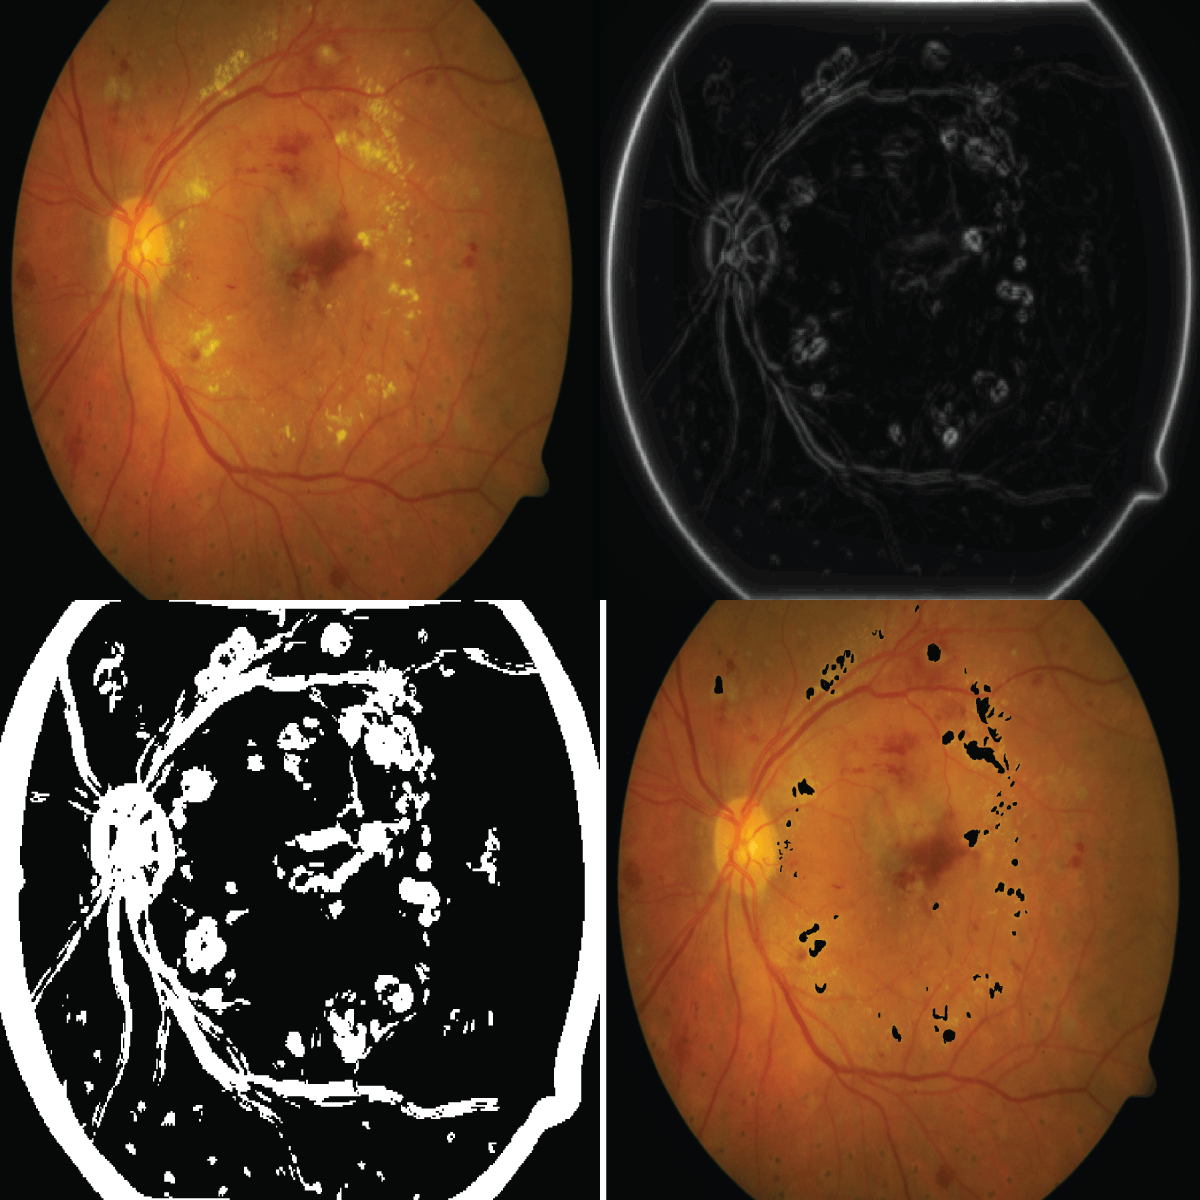

Fig. 4: Left: Original Image, Right: GIMAP, Down - Left: After Binarization, Down - Right: Final detected Exudate

Fig. 4 shows exudate detection intermediate and final step results. First row shows the original image and its corresponding GIMAP, where as in second row image obtained after binarization and final detection result is depicted. From this Figure it can be noticed that GIMAP respones to retinal features such as the optic disc, the blood vessels etc and performance of postprocessing steps are well observed from final detection result.